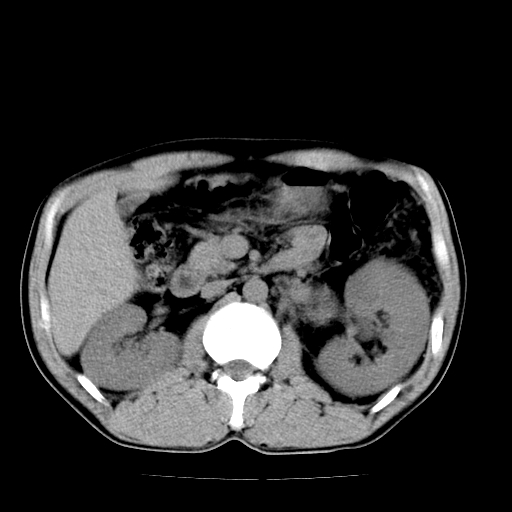

以下是引用天南地北在2007-4-30 13:36:00的发言:[br]支持慢性胰腺炎伴有假性囊肿

以下是引用andymaomao在2007-4-30 14:28:00的发言:[br]支持:1.慢性胰腺炎并假性囊肿形成可能;[br] 2.左肾形态稍增大,旋转不良。